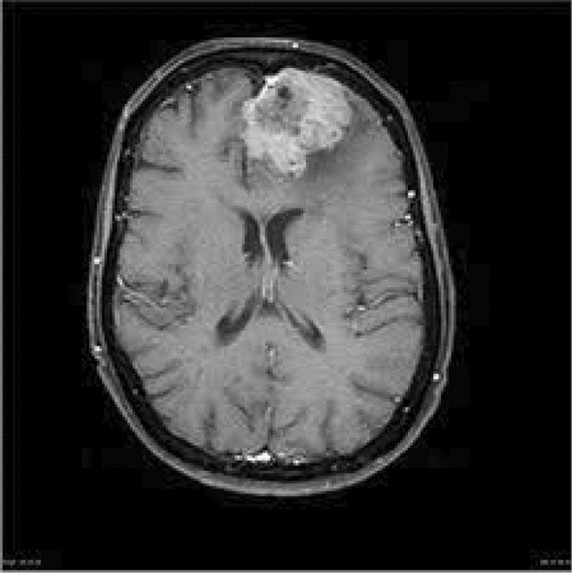

Our project, HappyMind, converts 2D MRI brain scans into interactive 3D visualizations. By leveraging AI, it helps highlight patterns and potential abnormalities that may not be immediately obvious in traditional scans. This allows for quicker analysis and a more comprehensive understanding of the data, especially in time-sensitive situations.

We built HappyMind by combining machine learning models with 3D rendering technologies. The system processes stacks of 2D MRI images and reconstructs them into a 3D brain model. We also integrated a backend powered by Gemini 3.1 to assist with data processing and analysis, and created an interface that allows users to interact with the 3D output in real time.